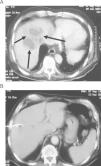

Absceso hepático secundario a la impactación de un cuerpo extraño en la pared colónica

Pyogenic liver abscess secondary to a foreign body penetration in the colonic wall